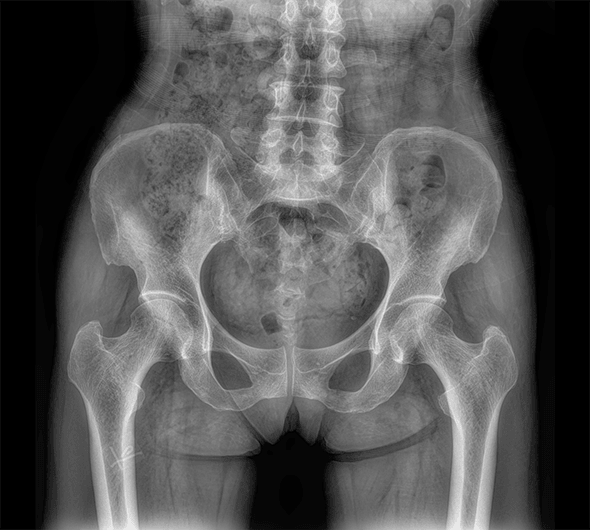

臨床圖像